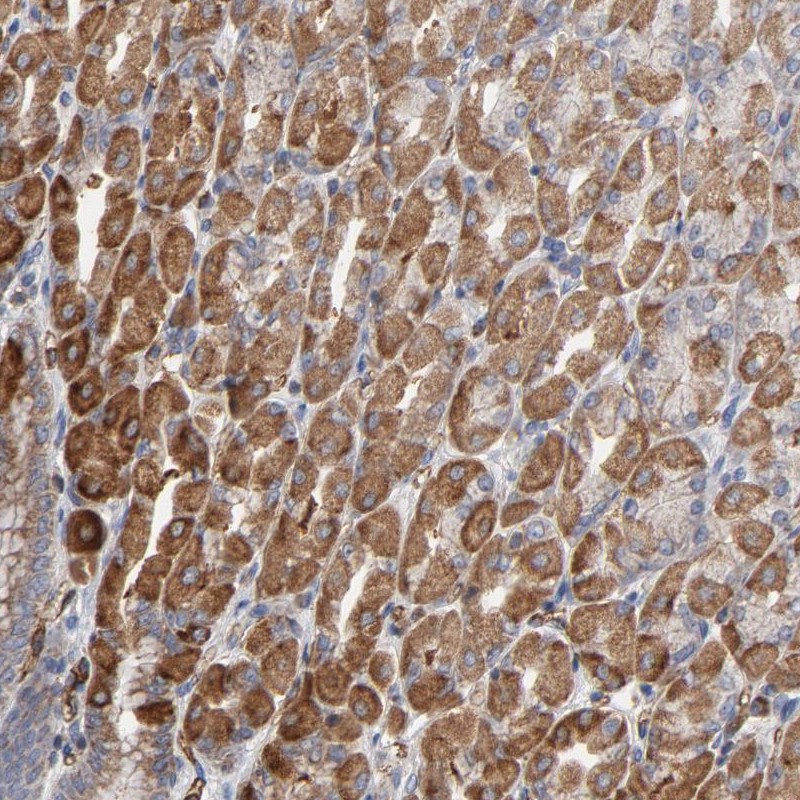

Immunohistochemical staining of human stomach shows strong cytoplasmic positivity in glandular cells.